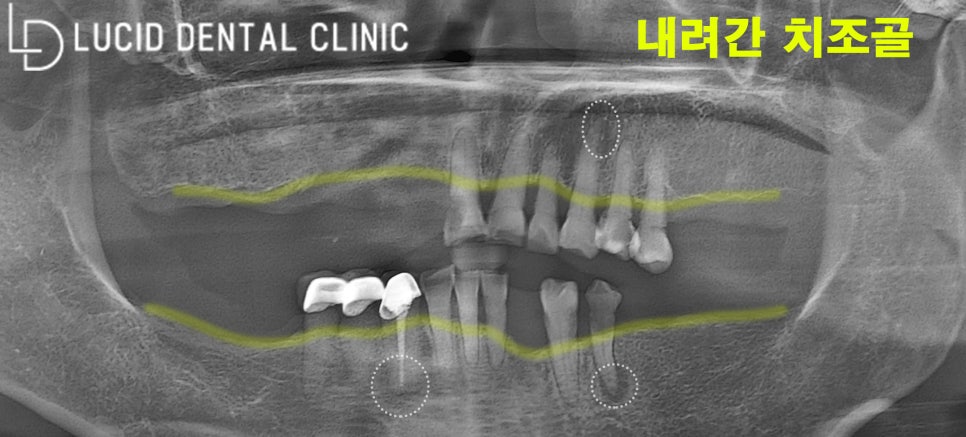

바로 파노라마 사진을 찍어봤습니다.

그런데, 제가 생각한 것보다

구강 상태가 꽤 좋지 않았는데요.

함께 사진을 보며

설명해 드리겠습니다.

우선 전체적으로 치아도 별로 없고,

치조골이 전부 내려갔어요.

게다가 치근단(치아 뿌리)에

염증이 심각한 상황입니다.